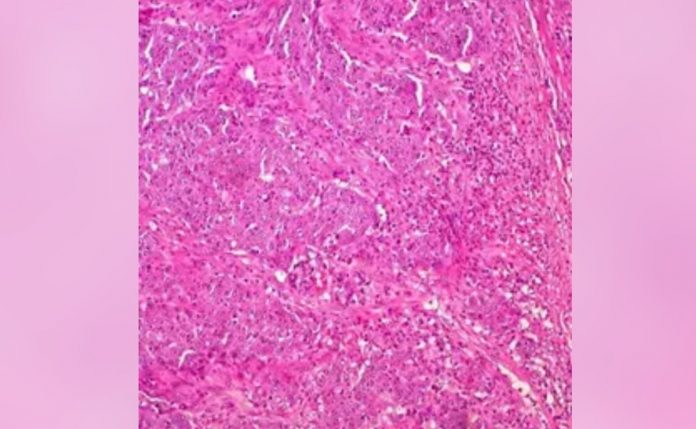

La investigación preclínica es un primer paso para demostrar que el virus oncolítico CF33 de City of Hope puede atacar tumores difíciles de tratar que “esposan” el sistema inmunológico y evitan que las células T activen el sistema inmunológico para matar las células cancerosas. Más específicamente, los investigadores demostraron en modelos de ratón que CF33 parece aumentar la expresión de PD-L1 en las células tumorales y hace que mueran de una manera que estimula la afluencia de células inmunes activadas.

“El CF33 infecta, se replica y destruye selectivamente las células cancerosas. Este estudio demuestra que un virus de diseño que creamos para infectar una amplia variedad de cánceres puede hacer que las células tumorales sean muy reconocibles para el sistema inmunológico”, explica.

Él, Warner y otros médicos-científicos de City of Hope están trabajando para convertir los “tumores fríos” resistentes al tratamiento en “tumores calientes” que pueden ser eliminados por un sistema inmunológico bien entrenado.

Para confirmar su hipótesis, los científicos de City of Hope probaron cuatro grupos: control sin tratamiento, anti-PD-L1 solo, CF33 solo y una combinación de CF33 y anti-PD-P1. Los resultados indicaron que un tratamiento combinado del virus oncolítico de City of Hope y anti-PD-L1 pareció ser más eficaz.